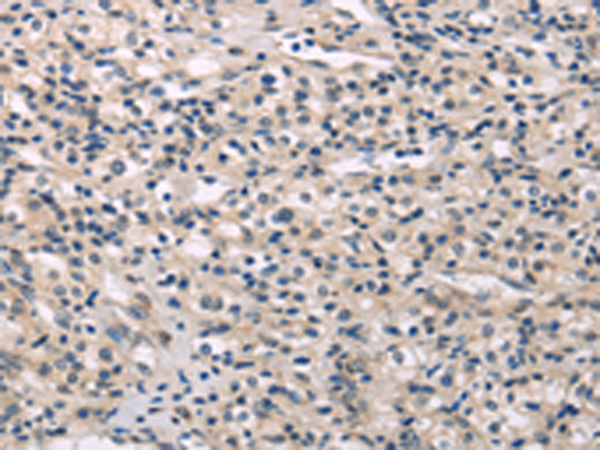

分类: 科研抗体货号: P08886别名: DESC1; TMPRSS11E2应用: IHC反应种属: Human